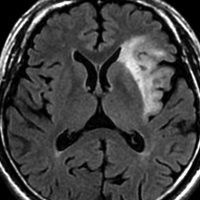

2010年無症状の時の画像です。こんなのを手術で摘出したら認知機能が落ちて人格が変わります。だから経過観察しました。

2015年のテモゾロマイドを開始する前の画像です。2014年にちょびっと生検術をして1p/19q欠失,IDH変異はわかっていました。2015年に全般発作を起こしたので治療を開始しました。テモゾロマイドを 2年 24コース続けました。乏突起膠腫は大きくなる時,てんかんを生じることが多いです。

2020年の画像です。腫瘍はかなり小さくなって再燃(再発)していません。てんかんも抑制されて発作はありません。無症状です。

この例は,手術も放射線治療もしないで,乏突起膠腫が10年以上,制御できることを示しています。また,テモゾロマイド治療でてんかん発作が少なくなることも有名な事実です。

でも,現実はこんなに甘くない?  2025年時点で,治癒を目指すなら低線量放射線治療を加えるべきと考えられています。

右前頭葉の乏突起膠腫グレード2です。46グレイとテモゾロマイドの治療で落ち着いていました。右側は初回治療後12年目の再発です。

とても限局性の再発でしたので,開頭手術で全摘出 supratotal resection しました。

オリゴには,浸潤性ではなくて,表面的で限局性の再発も多いです。でも多少は浸潤しているので,再度の再発の可能性は残ります。